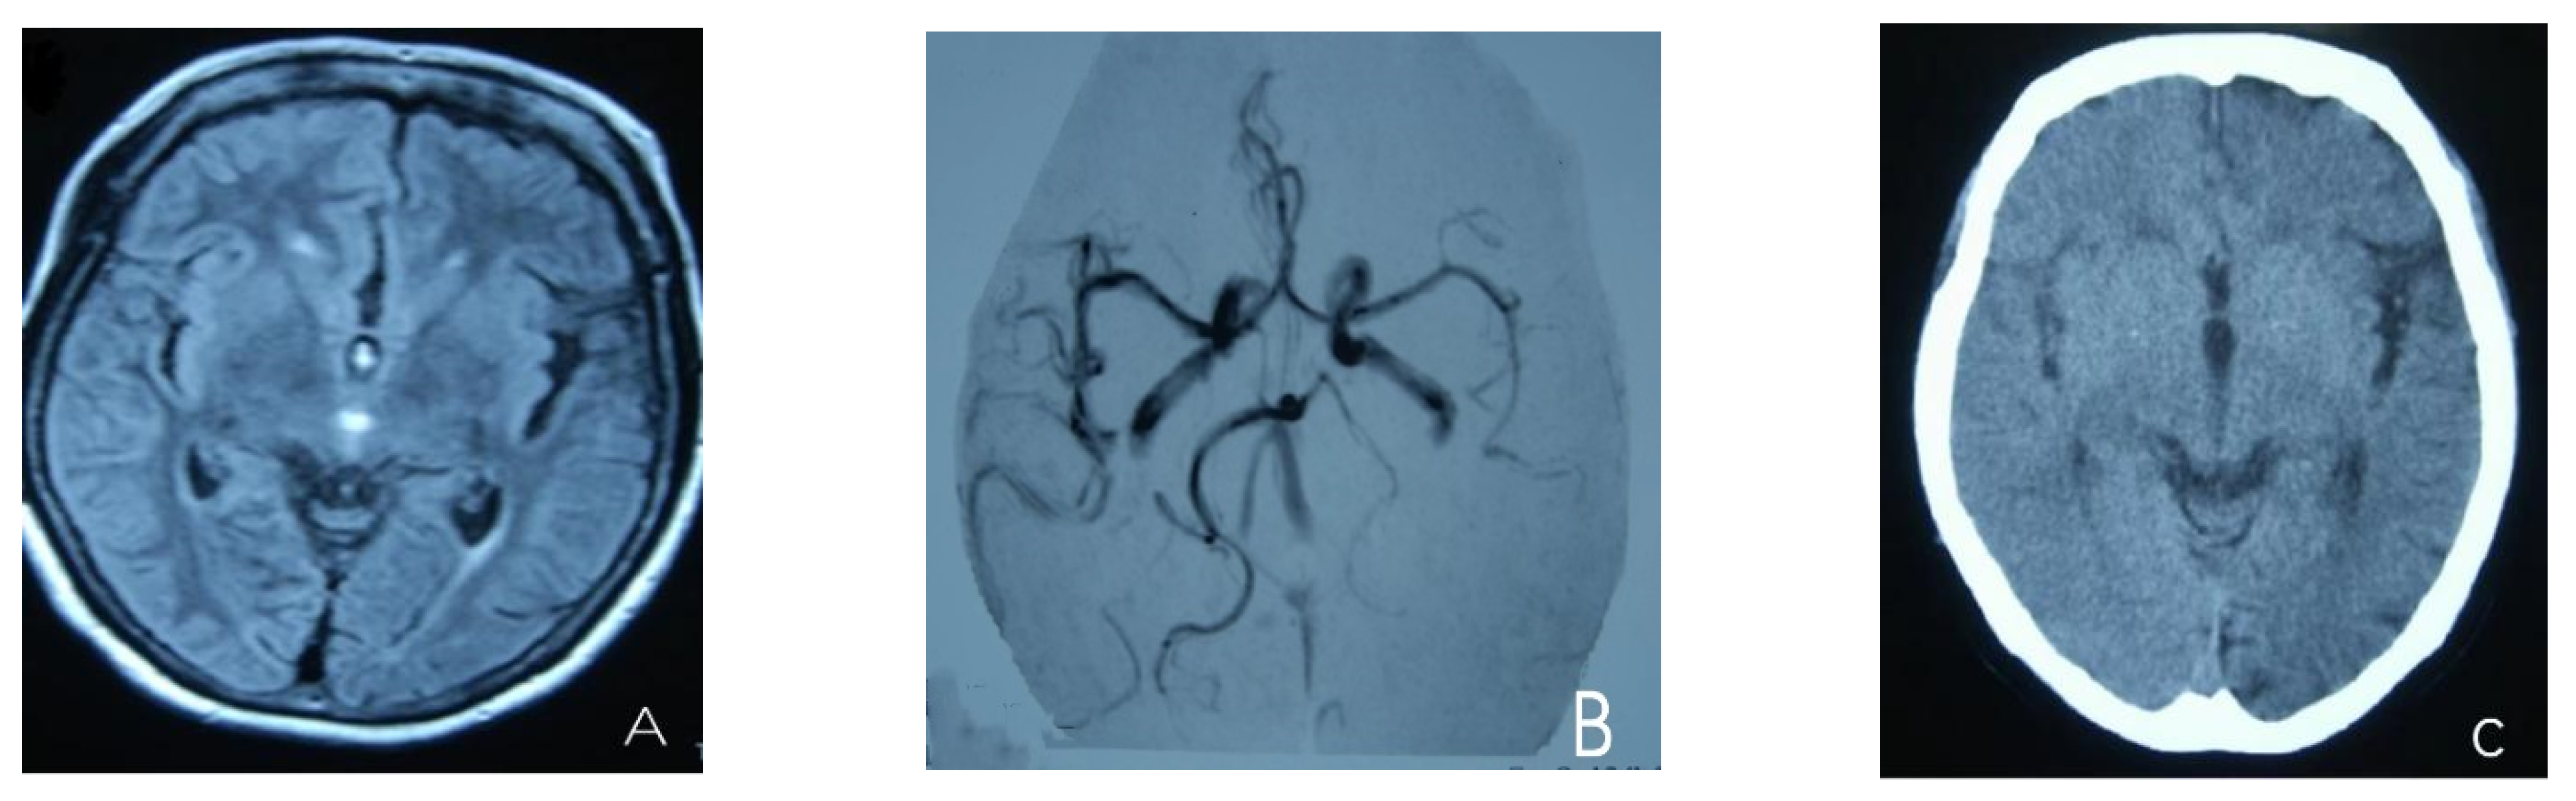

2. Case Presentation

- Roth, C.; Ferbert, A.; Huegens-Penzel, M.; Siekmann, R.; Freilinger, T. Multimodal imaging findings during severe attacks of familial hemiplegic migraine type 2. J. Neurol. Sci. 2018, 392, 22–27. [Google Scholar] [CrossRef] [PubMed]